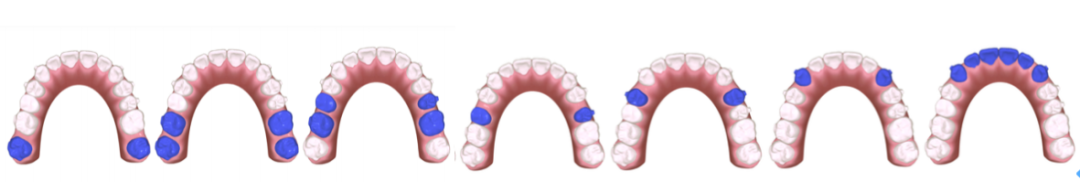

⽮状向:前牙先以12为基准排齐再内收2 ㎜,通过磨牙远移+前牙3~3不超0.3㎜ IPR获得间隙,前牙内收过程当中参考11保持转矩内收。下前牙内收过程当中保持转矩内收(参考41)、前牙正常覆盖结束。移动序列使用改良V-PATTERN’序列(如图1-9所示)每轮2㎜,前磨牙分开移动,5移动到位之后再移动4,均分⽮状向远移量, 后牙在远移过程当中增加冠远中轴倾角度,以根尖点为旋转中⼼(如图1-10所示)

上下颌初始与终末位置重叠。上颌以21为基准内收6㎜(如图1-11所示),下颌以31为基准内收3㎜(如图1-12所示)。内收过程当中要时刻关注前牙支抗(是否出现前牙唇倾)要根据前牙支抗情况,选择不同⼒值的皮筋牵引,需要注意的是,合理的移动序列比支抗钉更加重要。关注前牙支抗的同时也要关注后牙段,防⽌已经推到位的磨牙出现近中移动,有效的⽅法是在已经到位的磨牙制作TPA或使用间接支抗(如图1-12所示)。垂直向:该患者为均角,设计为通过伸长前磨牙压低后牙与下前牙整平下颌SPEE曲线,前牙正常覆合结束。SPEE曲线整平⽅式:对于⾼角患者、后部HE平面较陡的SPEE曲线主要通过压低后牙的⽅式整平。均角患者设计压低后牙与下前牙,伸长前磨牙的⽅式整平,低角患者希望更多通过升⾼后牙的⽅式整平SPEE曲线。⽔平向:以16、26为基准,不设计扩弓调整上下颌牙弓宽度。第⼀:参考Wala嵴(如图1-14所示),看颊侧是否有⾜够的骨量,通过测量FA点与 Wala Radge 的距离或参考CBCT进⾏判断)、磨牙的转矩(如图1-14所示),可以在电⼦扫描模型中的后视图当中进⾏观察(如图1-15)。后牙舌倾是扩弓的有利条件。如果磨牙已经是颊倾的状态,则不建议再设计扩弓,可在处⽅表当中向技师表明“以 16、26横向宽度为基准,维持现在的磨牙牙弓宽度”。